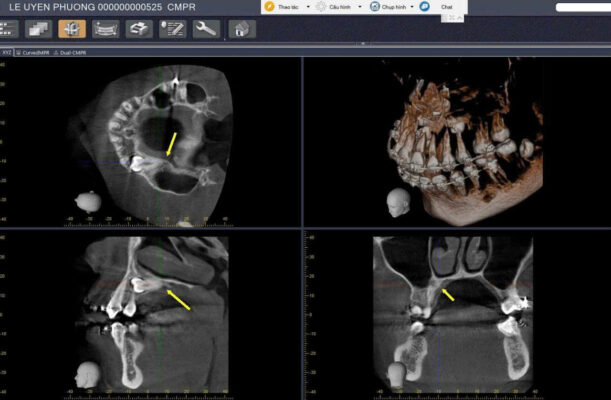

Phim X-quang quanh chóp, phim toàn cảnh (panorama) hoặc CBCT để xác định:

Vị trí, hướng mọc của răng ngầm.

Liên quan với răng kế cận, ống thần kinh, xoang hàm.